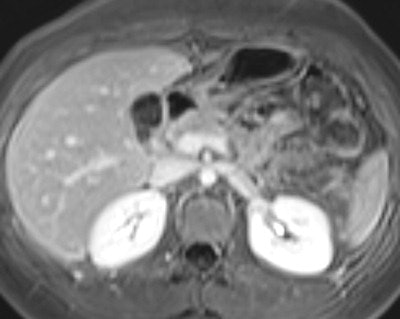

An 18-year-old female patient complained of abdominal pain, and Crohn's disease was suspected. Top: MR enterography axial fat-saturated true-FISP image demonstrates a target-like small bowel appearance of a small bowel intussusception in the left upper quadrant (white arrow). Bottom: Axial fat-saturated VIBE image after intravenous contrast medium acquired 6 min later at the same level shows no evidence of intussusception. A diagnosis of a transient small bowel intussusception was made. No evidence of Crohn's disease..Adequate luminal distension is vital to accurately assess the small bowel, and three groups of contrast agents can be used to achieve distension: positive, negative, and biphasic agents. Positive oral contrast agents appear hyperintense on all sequences, and are based on gadolinium-chelate, ferrous, or manganese ions. The high signal intensity of the lumen can interfere with the high signal intensity of the bowel wall after intravenous contrast medium administration. Negative oral contrast agents are based on iron oxide particles. They appear as hypointense on all sequences.